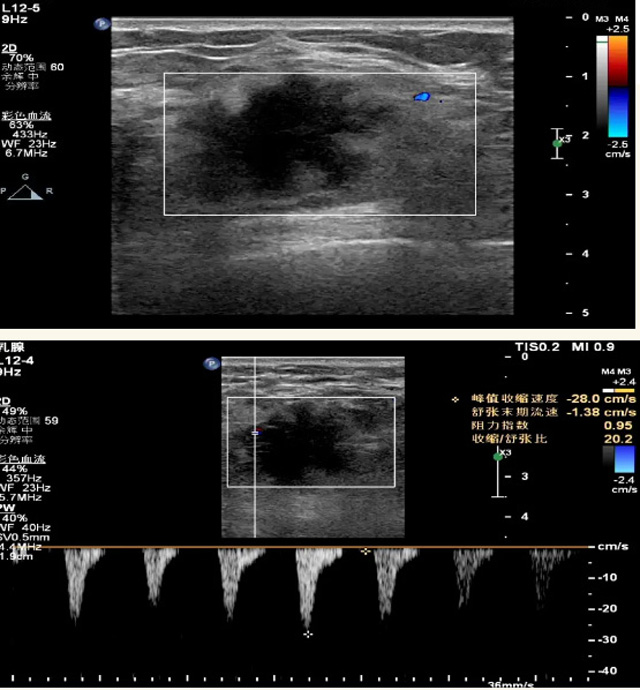

乳腺B超檢查無輻射,對囊性病變敏感,可以實時觀察病灶。超聲引導活檢跟手術前的定位。就是它對于微小的鈣化查出率比鉬靶稍微差點。磁共振MRI檢查也是是沒有輻射的,對備孕跟已經懷孕的人士比較友好。不用擔心這個輻射影響胎兒問題。對乳腺病灶敏感性較高,致密乳腺病灶、乳腺癌的復發,準確鑒別囊性及實性病變??梢詭椭R床醫生判斷惡性、良性病變。但是MRI磁共振對微小鈣化不明顯,微鈣化還是鉬靶靠譜點。檢查時間比較長,有偽影的影響。費用相對B超,鉬靶高很多。